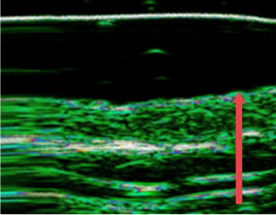

04. 皮肤真皮层厚度变化

可对因老化、频繁手术、外部刺激而变薄的皮肤真皮层进行改善

• radiesse_img11

施术前

• radiesse_img12

四个月后

(真皮层厚度增加12%)

• radiesse_img13

7个月后

(真皮层厚度增加27%)